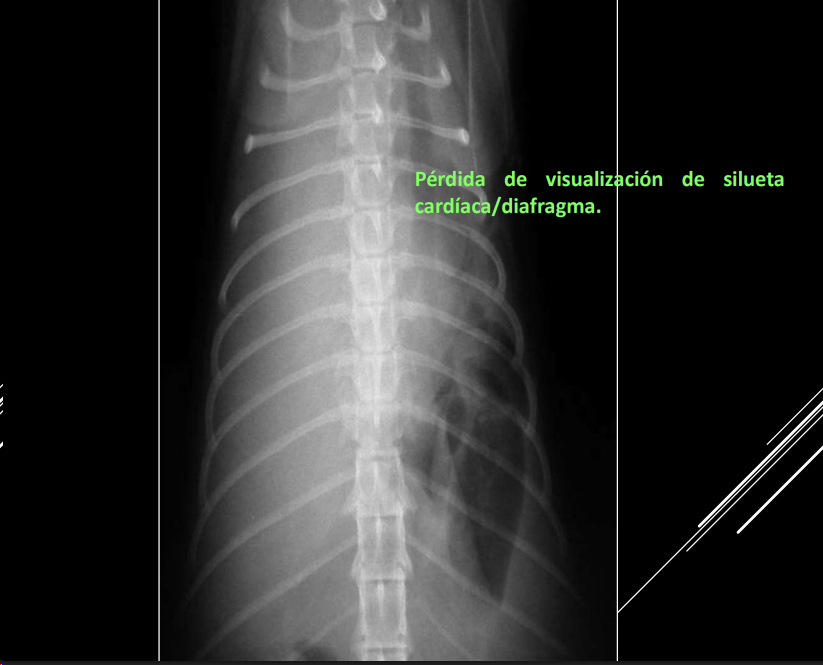

Efecto silhueta: cuando dos objetos de la misma densidad están en contacto, sus margenes no se pueden distinguir. No los distinguimos, los valoramos en grupo, buscamos cambios de tamaño, opacidad o de tamaño

- Alteraciones de posición del mediastino (Desplazamiento mediastino VD)

- Alteraciones de la anchura del mediastino (Derrame mediastinico o masa mediastinica VD)